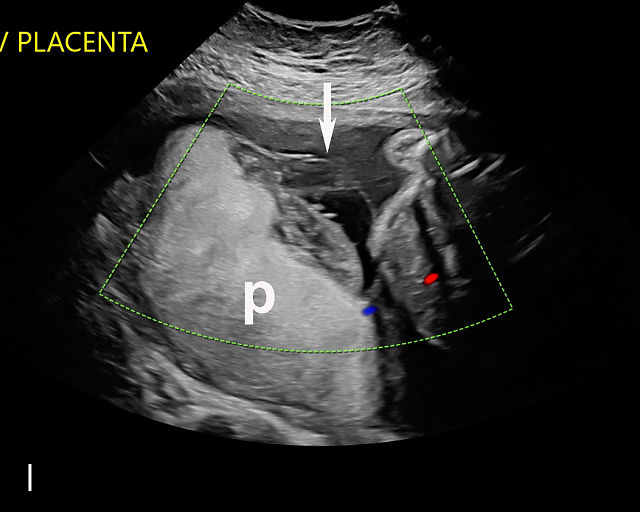

In the early first trimester, trophoblastic tissue appears as an echogenic ring encircling the gestational sac (Figure 1a). By the late first trimester, the placenta becomes recognizable as a distinct structure on ultrasound (Figure 1b). Initially, it presents as a homogeneous echogenic mass (Figure 1b–d) but undergoes progressive differentiation, becoming more heterogeneous as pregnancy advances from the second to third trimester (Figure 1e–g). By the third trimester, cotyledons become discernible, and in the late third trimester, calcifications frequently appear basally and around the cotyledons (Figure 1g).

1

Ultrasound images of development of the placenta (P/p). (a) Trophoblastic tissue appearing as an echogenic ring surrounding the gestational sac at 6 weeks' gestation. (b) Placenta at 12 weeks has become a discrete, uniformly echogenic mass. (c) Placenta at 17 weeks. (d) Placenta at 20 weeks. (e) Placenta at 27 weeks. (f) Placenta at 33 weeks. Increasingly, differentiation and heterogeneous appearance is seen, with demarcation of the cotyledons. Basal calcifications are beginning to appear. (g) Placenta at 40 weeks, showing a distinctly heterogeneous appearance, with clear demarcation of the cotyledons and presence of calcifications.